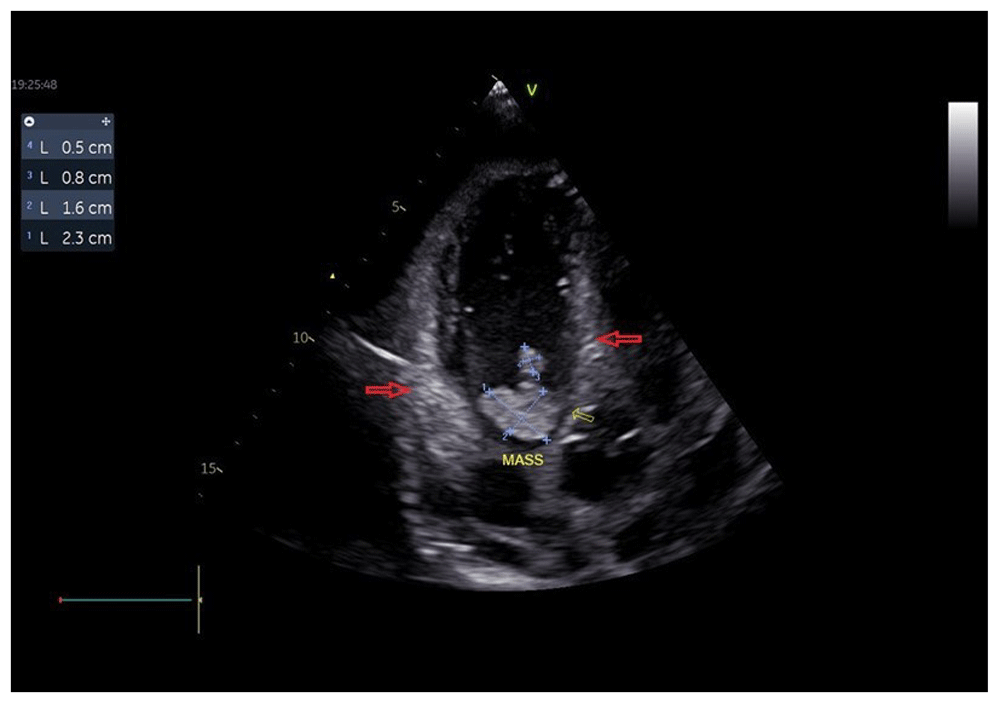

The patient was presented with chest discomfort and general weakness. He was hypotensive and bradycardic with blood pressure of 80/40 mmHg, regular heart rate of 44 beats per minute, respiratory rate of 18 breaths per minute, and oxygen saturation of 97% on room air. Chest auscultation was clear, and no murmurs heard. Electrocardiogram showed CHB with a junctional escape rhythm at 44 bpm (Figure 1). Echocardiography showed normal left ventricle kinetic, normal left ventricular ejection fraction (62%), and normal right ventricle systolic function. There were moderate pericardial effusion and intracardiac masses (2.1 × 0.9 cm and 1.8 × 0.8 cm) in the right atrial and septal leaflet of tricuspid. Hyperechoic areas in the annulus of tricuspid, lateral wall of right atrium and right ventricle, and interventricular septum were also found in an echocardiogram (Figure 2 and Figure 3). Laboratory finding revealed anemia (hemoglobin 8.5 g/dL; normal range 13.3-16.6 g/dL), leukocytosis (white blood count 18,470/mL; normal range 3,370-10,000/mL), hypoalbuminemia (albumin 2.6 g/dL; normal range 3.4-5.0 g/dL), hypokalemia (potassium 3.4 mmol/L; normal range 3.5-5.1 mmol/L), and hypercalcemia (calcium 16.2 mg/dL, corrected calcium 16.9 mg/dL; normal range 8.6-10.3 mg/dL).

Hyperechoic areas were found in the annulus of tricuspid, lateral wall of right atrium and right ventricle, and interventricular septum (red arrows).

Valves are an uncommon site for metastasis because of the absence of vessels in the physiological valvular stroma and the constant cusp motion. Bussani et al. reported, out of over a thousand of postmortem examination, there was only one case of valve involvement16. The mass in the septal leaflet of tricuspid valves appeared in echocardiography examination in this patient showed valve involvement of cardiac metastasis.

Cardiac masses in our case presented with features favoring tumor, such as echo density similar to myocardium, normal wall motion, valvular lesion, no history suggestive of coronary artery disease, and a clinical history of oral cancer as primary site suspected to metastasize to the heart.